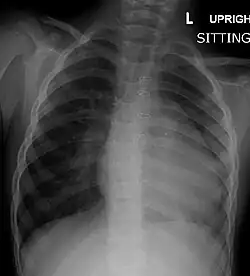

| Right ventricular hypertrophy | The right ventricle is more muscular than normal, causing a characteristic boot-shaped (coeur-en-sabot) appearance as seen by chest X-ray. Due to the misarrangement of the external ventricular septum, the right ventricular wall increases in size to deal with the increased obstruction to the right outflow tract. This feature is now generally agreed to be a secondary anomaly, as the level of hypertrophy tends to increase with age.[45] |

Chest radiograph

Before more sophisticated techniques became available, chest X-ray was the definitive method of diagnosis. The abnormal "coeur-en-sabot" (boot-like) appearance of a heart with tetralogy of Fallot is classically visible via chest X-ray, although most infants with tetralogy may not show this finding.[50] The boot like shape is due to the right ventricular hypertrophy present in TOF. Lung fields are often dark (absence of interstitial lung markings) due to decreased pulmonary blood flow.[51]: 171–172